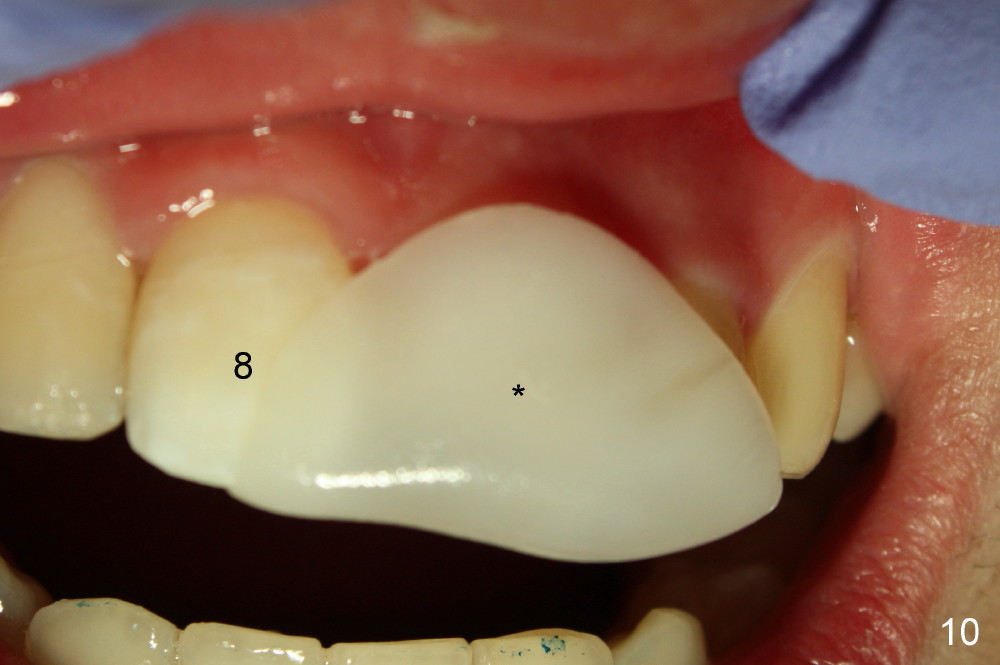

The patient returned to finish RCT 1.5 months later (Fig.6). Gutta percha was removed as much (high) as possible (Fig.7 >). In order to prevent butterfly rubber dam clamp interference in access and GP removal, smaller clamps should be placed in the neighboring teeth (Fig.8). When RCT was done, the tooth #9 was still the darkest (Fig.9). Thermoplastic tab was used to make local external bleaching tray (Fig.10 *). The patient and his mother were instructed to do external and internal bleaching daily.